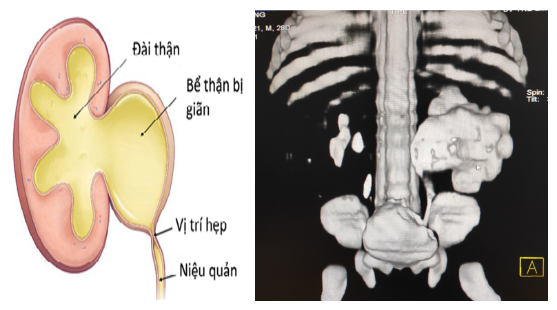

Hẹp khúc nối bể thận - niệu quản là một bất thường ở phần nối giữa bể thận và niệu quản, gây cản trở dòng nước tiểu từ thận xuống niệu quản và bàng quang, nước tiểu bị ứ đọng ở thận sẽ gây giãn bể thận, gây nên tình trạng thận ứ nước. Thận ứ nước nhiều và kéo dài sẽ gây suy giảm chức năng hoạt động của thận dẫn đến suy thận.

Hình ảnh chụp CT chẩn đoán hẹp khúc nối bể thận - niệu quản ở một bệnh nhi.

- Chụp cắt lớp vi tính giúp đánh giá chức năng thận và dựng hình được chính xác vị trí hẹp.